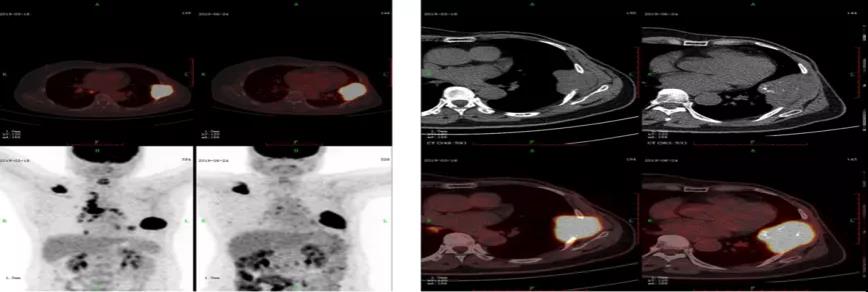

治疗接近3个月的复查:2019.6.24 PET-CT首次复查评估,考虑右侧颈部、纵膈、双肺门、右肺下叶转移灶退缩,SUV值下降。右侧肩胛骨转移、左侧胸壁转移伴有肋骨病理性骨折病灶变大,SUV值下降(胸壁肿物7.7*4.6cm,SUV12.4)(原胸壁肿物5.8*4.5cm,SUV17.2)。

2019.10.28 PET-CT复查评估,右侧颈部、纵膈、双肺门、右肺下叶转移灶基本都退缩,SUV值接近正常。右侧肩胛骨转移、左侧胸壁转移伴有肋骨病理性骨折病灶变小,SUV值下降(胸壁肿物3.9*2.5cm,SUV3.1)。